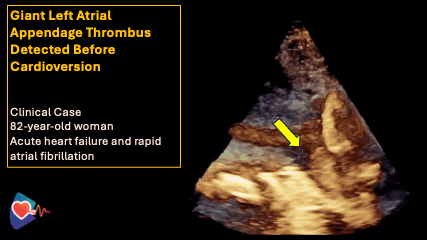

Echocardiography - Heart